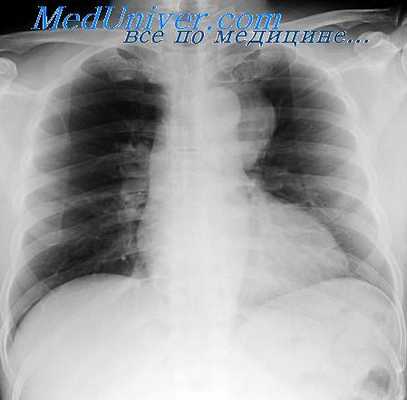

Дермоидные кисты и тератомы имеют довольно специфическую рентгенологическую картину. К числу наиболее характерных рентгенологических признаков относится локализация дермоидных кист и тератом. Известно, что последние, как правило, располагаются в переднем средостении.

Но в отличие от многих других локализующихся здесь опухолей дермоидные кисты и тератомы обычно располагаются непосредственно за грудиной в ретро-стернальном пространстве и чаще всего в средней трети длинника средостения (у 15 из 21 больного G. И. Волкова, у 8 из 12 наших больных). Редко отмечается локализация в нижнем отделе средостения или на всем его протяжении при больших размерах дермоида.

По отношению к средней линии патологическая тень в 80—90% случаев (Дезев и Дюмон) имеет одностороннее расположение: по одним авторам — чаще справа (Б. Г. Стучинский, Дезев и Дюмон), по другим — чаще слева (наблюдения С. И. Волкова и наши). Редко дермоиды располагаются срединно (в 4,2% случаев, по Б. Г. Стучинскому). При этом они могут выходить за оба контура срединной тени.

В большинстве случаев тень дермоидов имеет овальную форму с косо расположенным длинником по отношению к длиннику срединной тени, реже неправильно округлую форму. При росте дермоидной кисты в междолевую щель длинник ее овала принимает горизонтальное положение (А. Е. Прозоров). Размеры патологической тени могут колебаться в широких пределах — от небольших до громадных. В последнем случае бывает затемнена почти вся половина грудной клетки.

Дермоидные кисты средостения чаще всего располагаются в передневерхнем отделе средостения в пространстве, ограниченном спереди задней поверхностью грудины и парастернальными хрящами, сзади — крупными сосудами грудной полости, сверху — зобной железой и снизу — передней поверхностью перикарда. Рост кисты наблюдается вправо или влево от средней линии. У ряда наших больных кисты располагались в нижних отделах средостения.